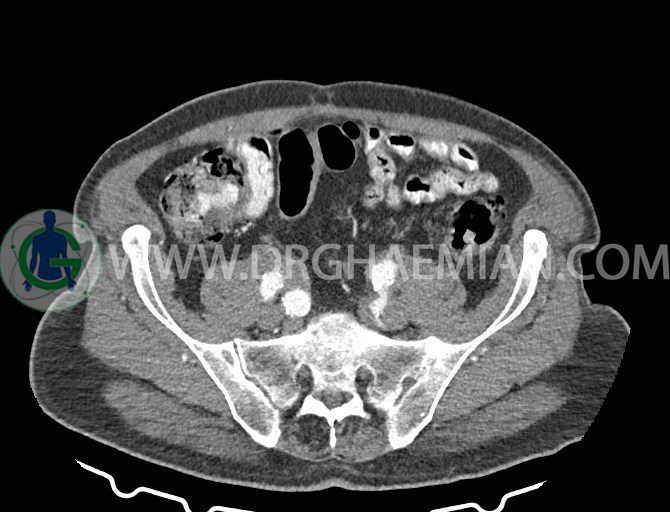

سی تی اسکن لگن یکی از روش های تصویربرداری با سی تی اسکن است. این روش با استفاده از تشعشعات تصاویر عرضی از ناحیه شکمی ایجاد میکند. در این کیس ديورتيكولوزيس، کیست های کورتیکال در هر دو کلیه، لنفادنوپاتی، کلسیفیکاسیون دیواره آئورت و شریان ایلیاک، تغییرات DJD ناحیه توراکولومبار و پروستات بزرگتر از عادی دیده می شود.

– کلسيفيکاسيون ديواره آئورت و شريان ها ايلياک همراه با نشانه هاي ترومبوز مورال در بيفورکاسيون ائورت با امتداد به پروگزيمال هاي شريان هاي ايلياک

لنفادنوپاتي به ابعاد mm 22 x 25 مجاور شريان ايلياک خارجي چپ و به ابعاد mm 17 x 28 مجاور شريان ايلياک خارجي راست

– پروستات به ابعاد mm 45 x 54، بزرگ تر از نرمال